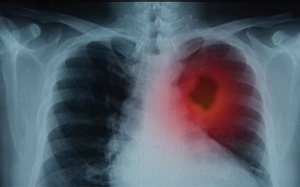

Ung thư phổi không còn là căn bệnh xa lạ trong cuộc sống hiện nay. Không ít trường hợp người bệnh phát hiện mắc ung thư phổi đều đã ở giai đoạn cuối.

Khi tiến triển đến giai đoạn cuối, người bệnh ung thư phổi đối mặt với nhiều nguy hiểm. Hiểu rõ về giai đoạn này giúp người bệnh chuẩn bị tốt về cả sức khỏe lẫn tinh thần.